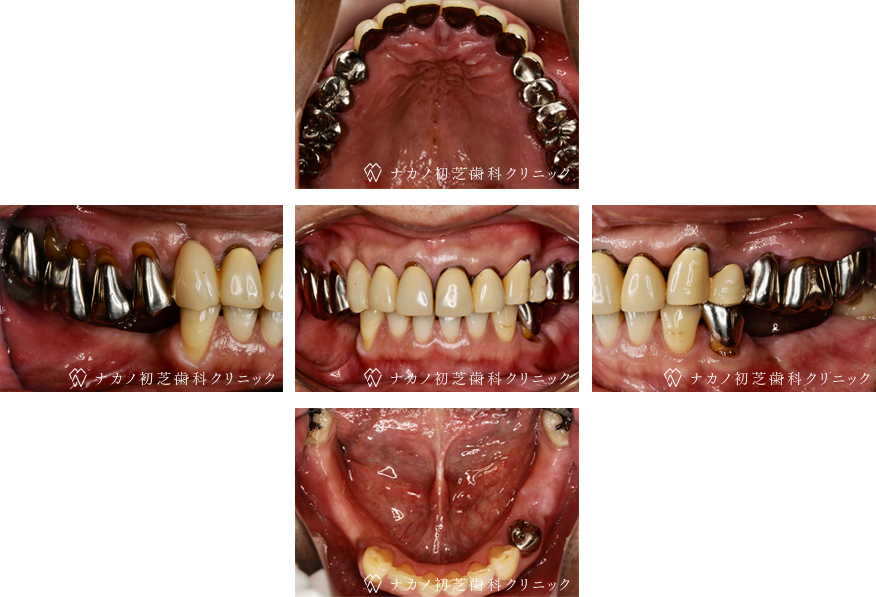

インプラント・13本 (60代女性)

-

BEFORE

AFTER

年齢 60代女性

治療内容 インプラント治療13本(骨造成の併用)

インプラント治療とは、歯を抜いた所にチタン製の人工歯根を埋入し、その上に歯を入れる方法です。骨を増やすことで、より審美的に治療が出来ました。費用 1本 400,000円(税込 440,000円)

リスク・副作用

腫れ・疼痛・違和感を感じるなどの症状を生じることがあります。